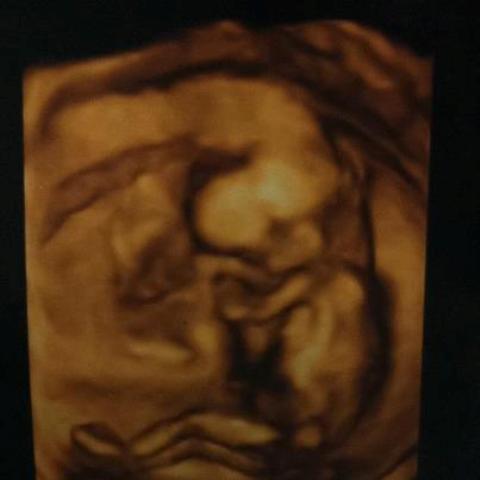

Դերասան Հովհաննես Ազոյանի կինը` Մերի Ազոյանն, օրեր առաջ ամուսնու ֆեյսբուքյան էջում տեղադրել է իրենց երկրորդ փոքրիկի առաջին` ուլտրաձայնային սարքավորման միջոցով արված լուսանկարներից մեկը: Հովիկը և Մերին արդեն ունեն մեկ դուստր և սպասում են, փաստորեն, ըստ հետազոտության արդյունքների` երկրորդ դստերը: Ի դեպ, Մերին երկրորդ փոքրիկի անունը կարծես թե որոշել է, քանի որ նրան անվանել է Վիկի: